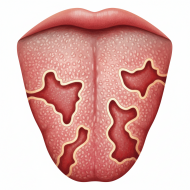

Географический язык — состояние, которое часто вызывает тревогу у пациентов из-за необычного внешнего вида языка. Пятна, изменение рельефа, «рисунок» на поверхности могут выглядеть пугающе, однако далеко не всегда это признак серьёзного заболевания. В этой статье разберёмся, что такое географический язык, почему он появляется, когда требуется лечение и в каких случаях важно обратиться к врачу.

Географический язык (медицинское название — десквамативный глоссит) — это доброкачественное воспалительное состояние слизистой оболочки языка. Оно проявляется участками слущивания эпителия, из-за чего на поверхности языка появляются пятна с чёткими границами.

На языке появляются:

Характерная особенность — пятна могут менять форму, размер и расположение в течение дней или недель. Именно из-за этого внешнего сходства с географической картой состояние и получило своё название.